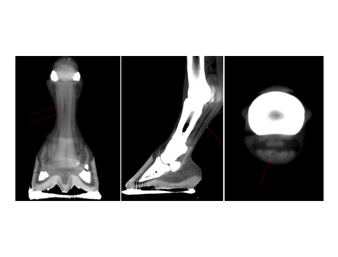

The Asto Equina is a dual-limb, fan-beam CT unit that is capable of imaging equine limbs from the carpus/tarsus down to the foot, as well as the equine head and neck. Scan acquisition is fast and able to be completed in a standing, sedated horse. This fan-beam unit captures excellent bone and soft tissue detail, allowing for diagnosis of a wide variety of pathologies.

In this presentation, Dr. Jack Caldwell of Virginia Equine Imaging (VEI) discusses how Asto CT’s standing fan-beam CT is being used in private equine practice to improve diagnostics, treatment planning, and outcomes for performance horses. Dr. Caldwell walks through real-world clinical cases involving sport horses, jumpers, dressage horses, and eventers—highlighting how standing CT has enhanced the evaluation of complex lameness, distal limb pathology, neck conditions, head trauma, and surgical planning. These cases demonstrate how CT imaging can reveal pathology that may be underestimated or missed with radiographs, ultrasound, or low-field MRI alone.